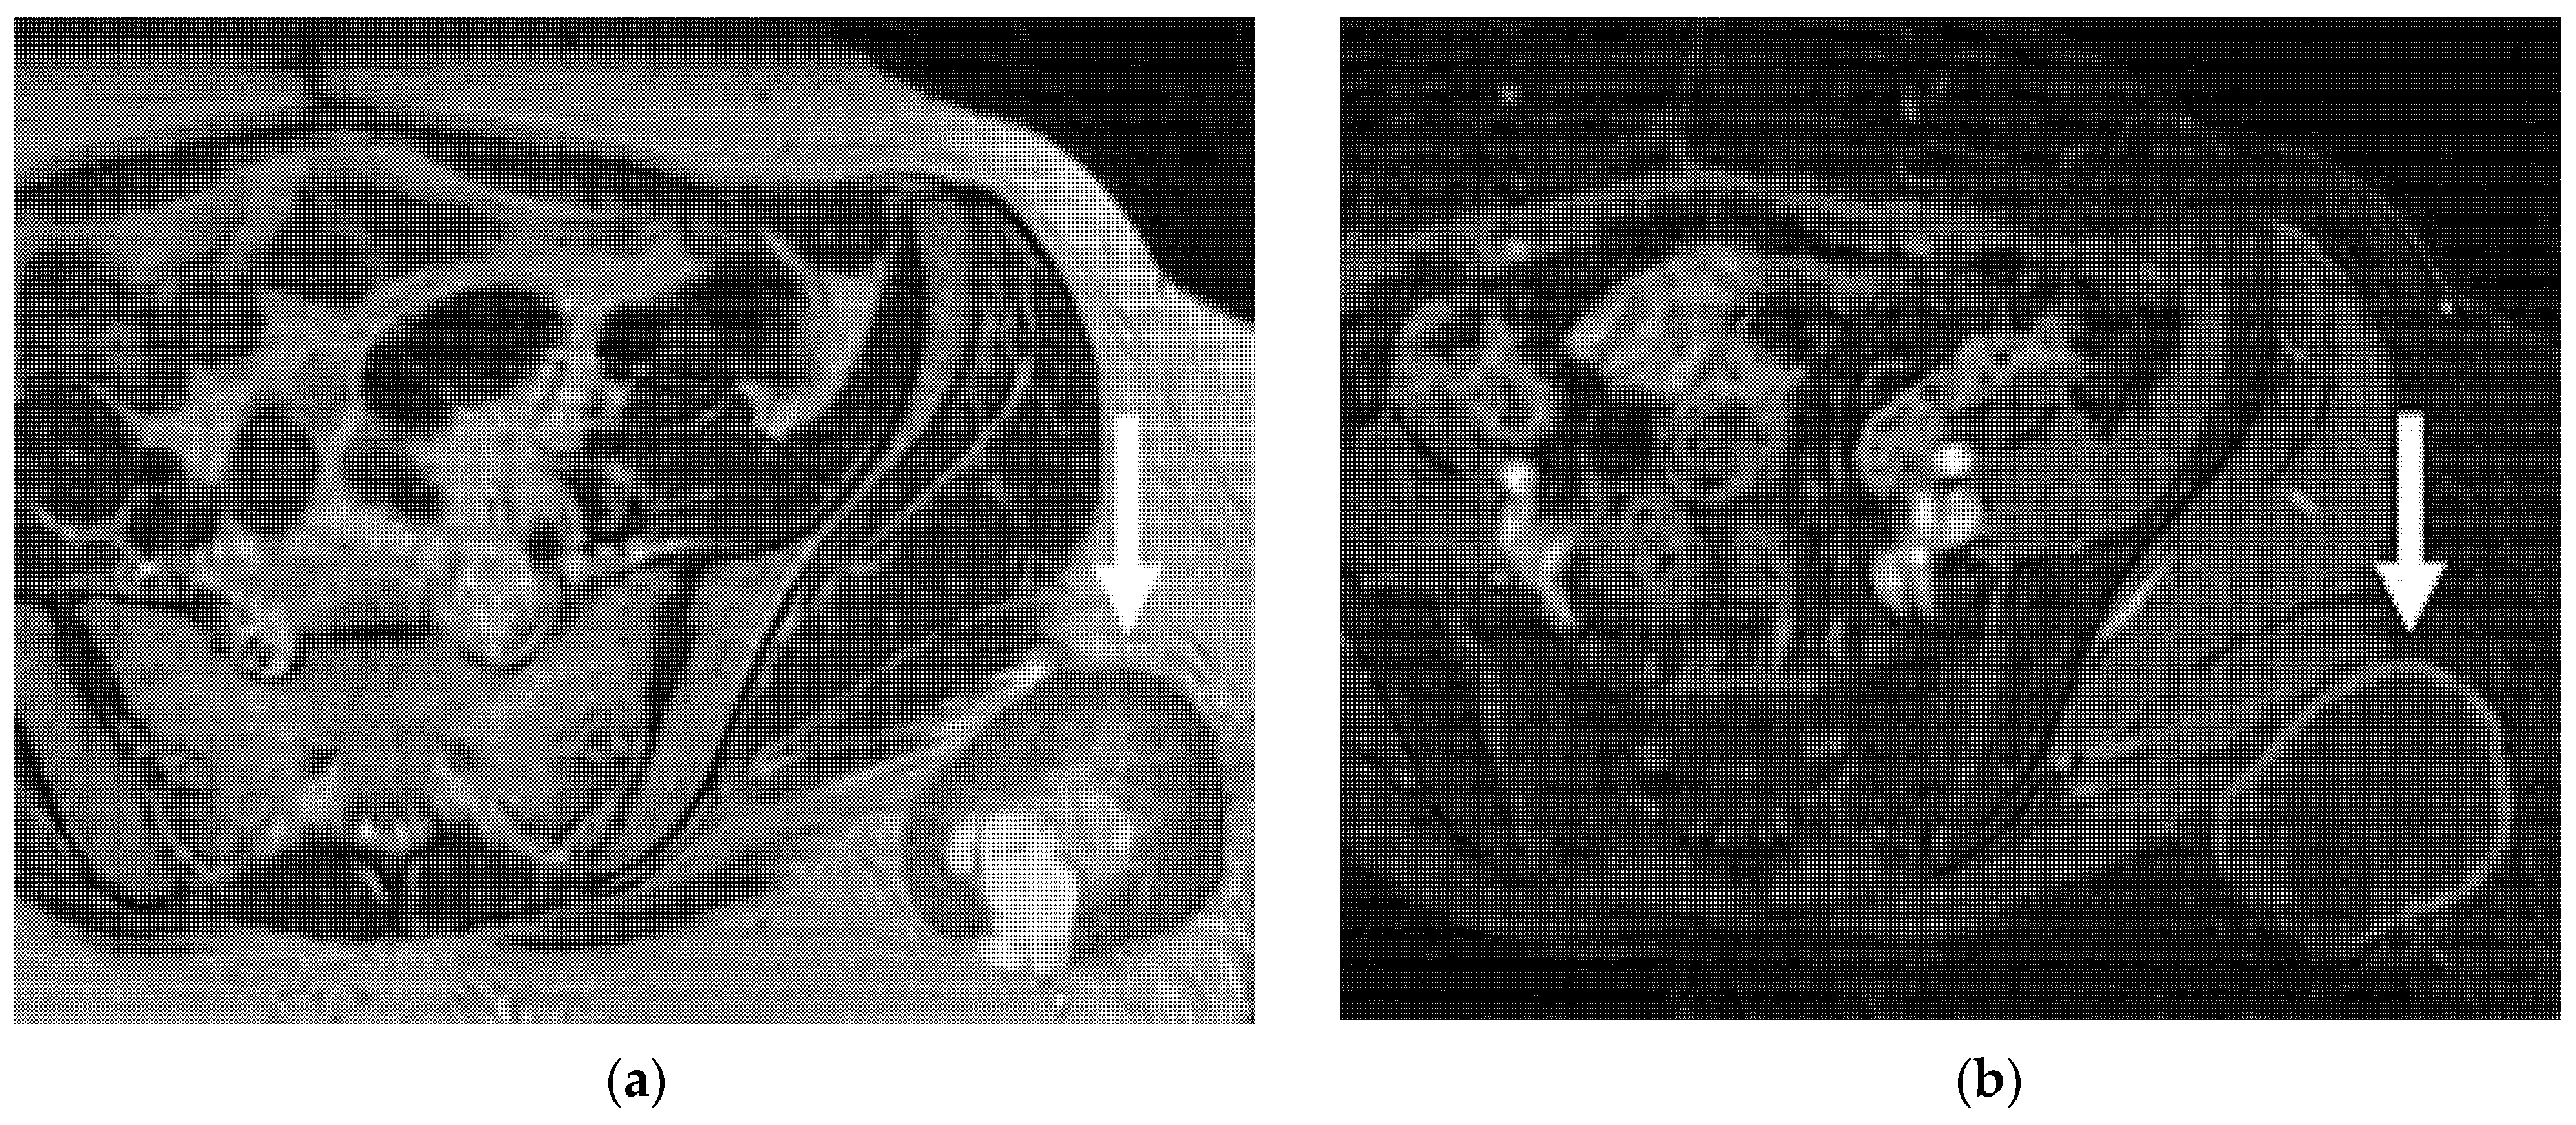

6.2. Abdominal and Extra-Abdominal Recurrence

| Abdominal and extra-abdominal recurrence |